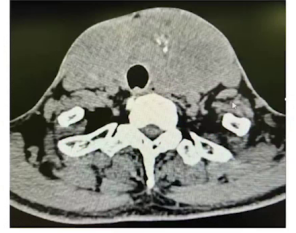

(3)影像学检查

ECT显像见甲状腺弥漫性病变,摄碘率增高。CT平扫显示甲状腺增大、密度不均、有钙化及颅面骨和上段颈椎骨纤维结构不良。

CT平扫显示甲状腺增大、密度不均、有钙化及颅面骨和上段颈椎骨纤维结构不良。